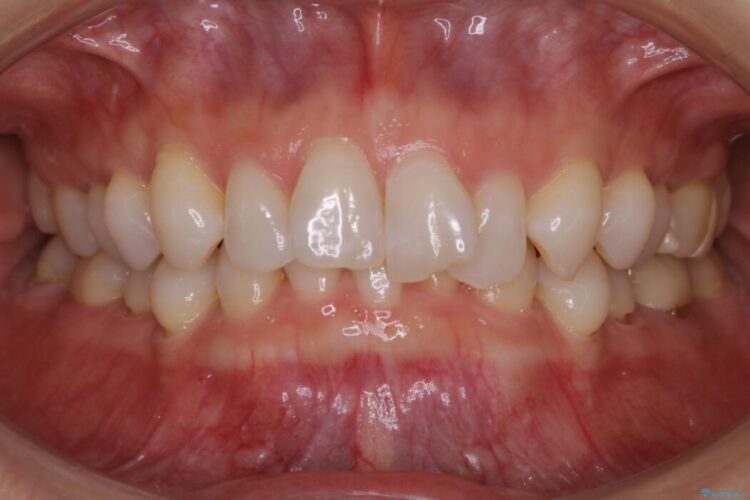

前歯のガタつきの治療を目的に来院されました。

主訴としては矯正治療にて歯列を整えることでした。

噛み合わせも改善され、一番最初の目的であった歯列もきれいに整いご満足いただけました。